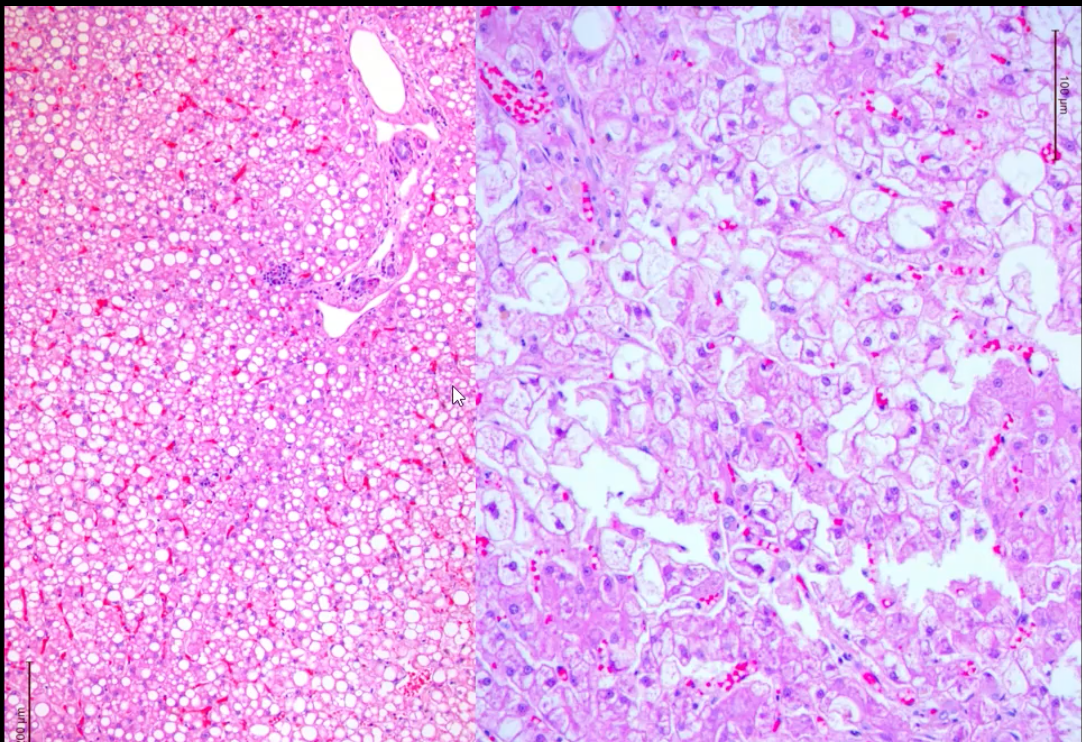

how do we know this is the liver?

what is the difference between these two slides of the liver

histologically what is the difference between hepatic lipidosis and a glycogen accumulation in the liver

in hepatic lipidosis the nuclei is often pushed to periphery and vacuoles have distinct borders

and while glycogen accumulation in the liver the nuclei stays central and vacuoles have irregular or indistinct borders